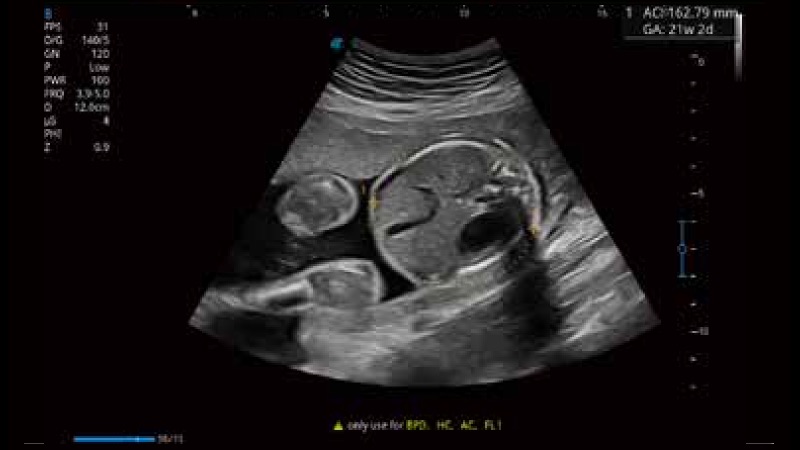

容积探头

凭借开立医疗先进的成像技术和优异的探头技术提供的清晰的图像表现,您可以更自信地做出临床决策。